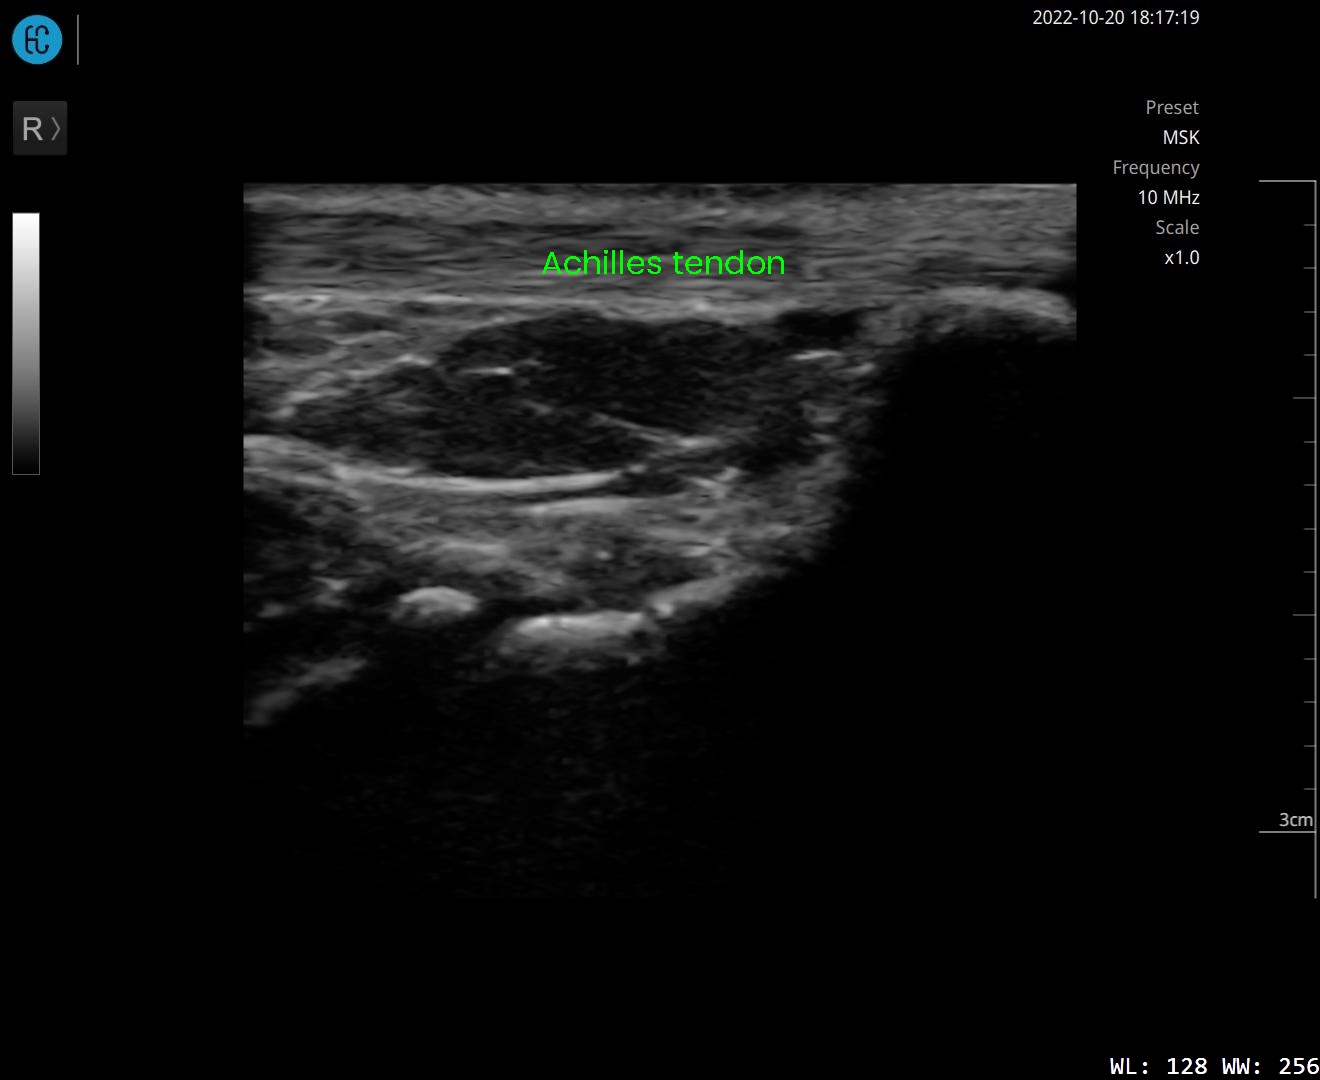

SONON 500L ecografía 1 SONON 500L ecografía 2 SONON 500L ecografía 3